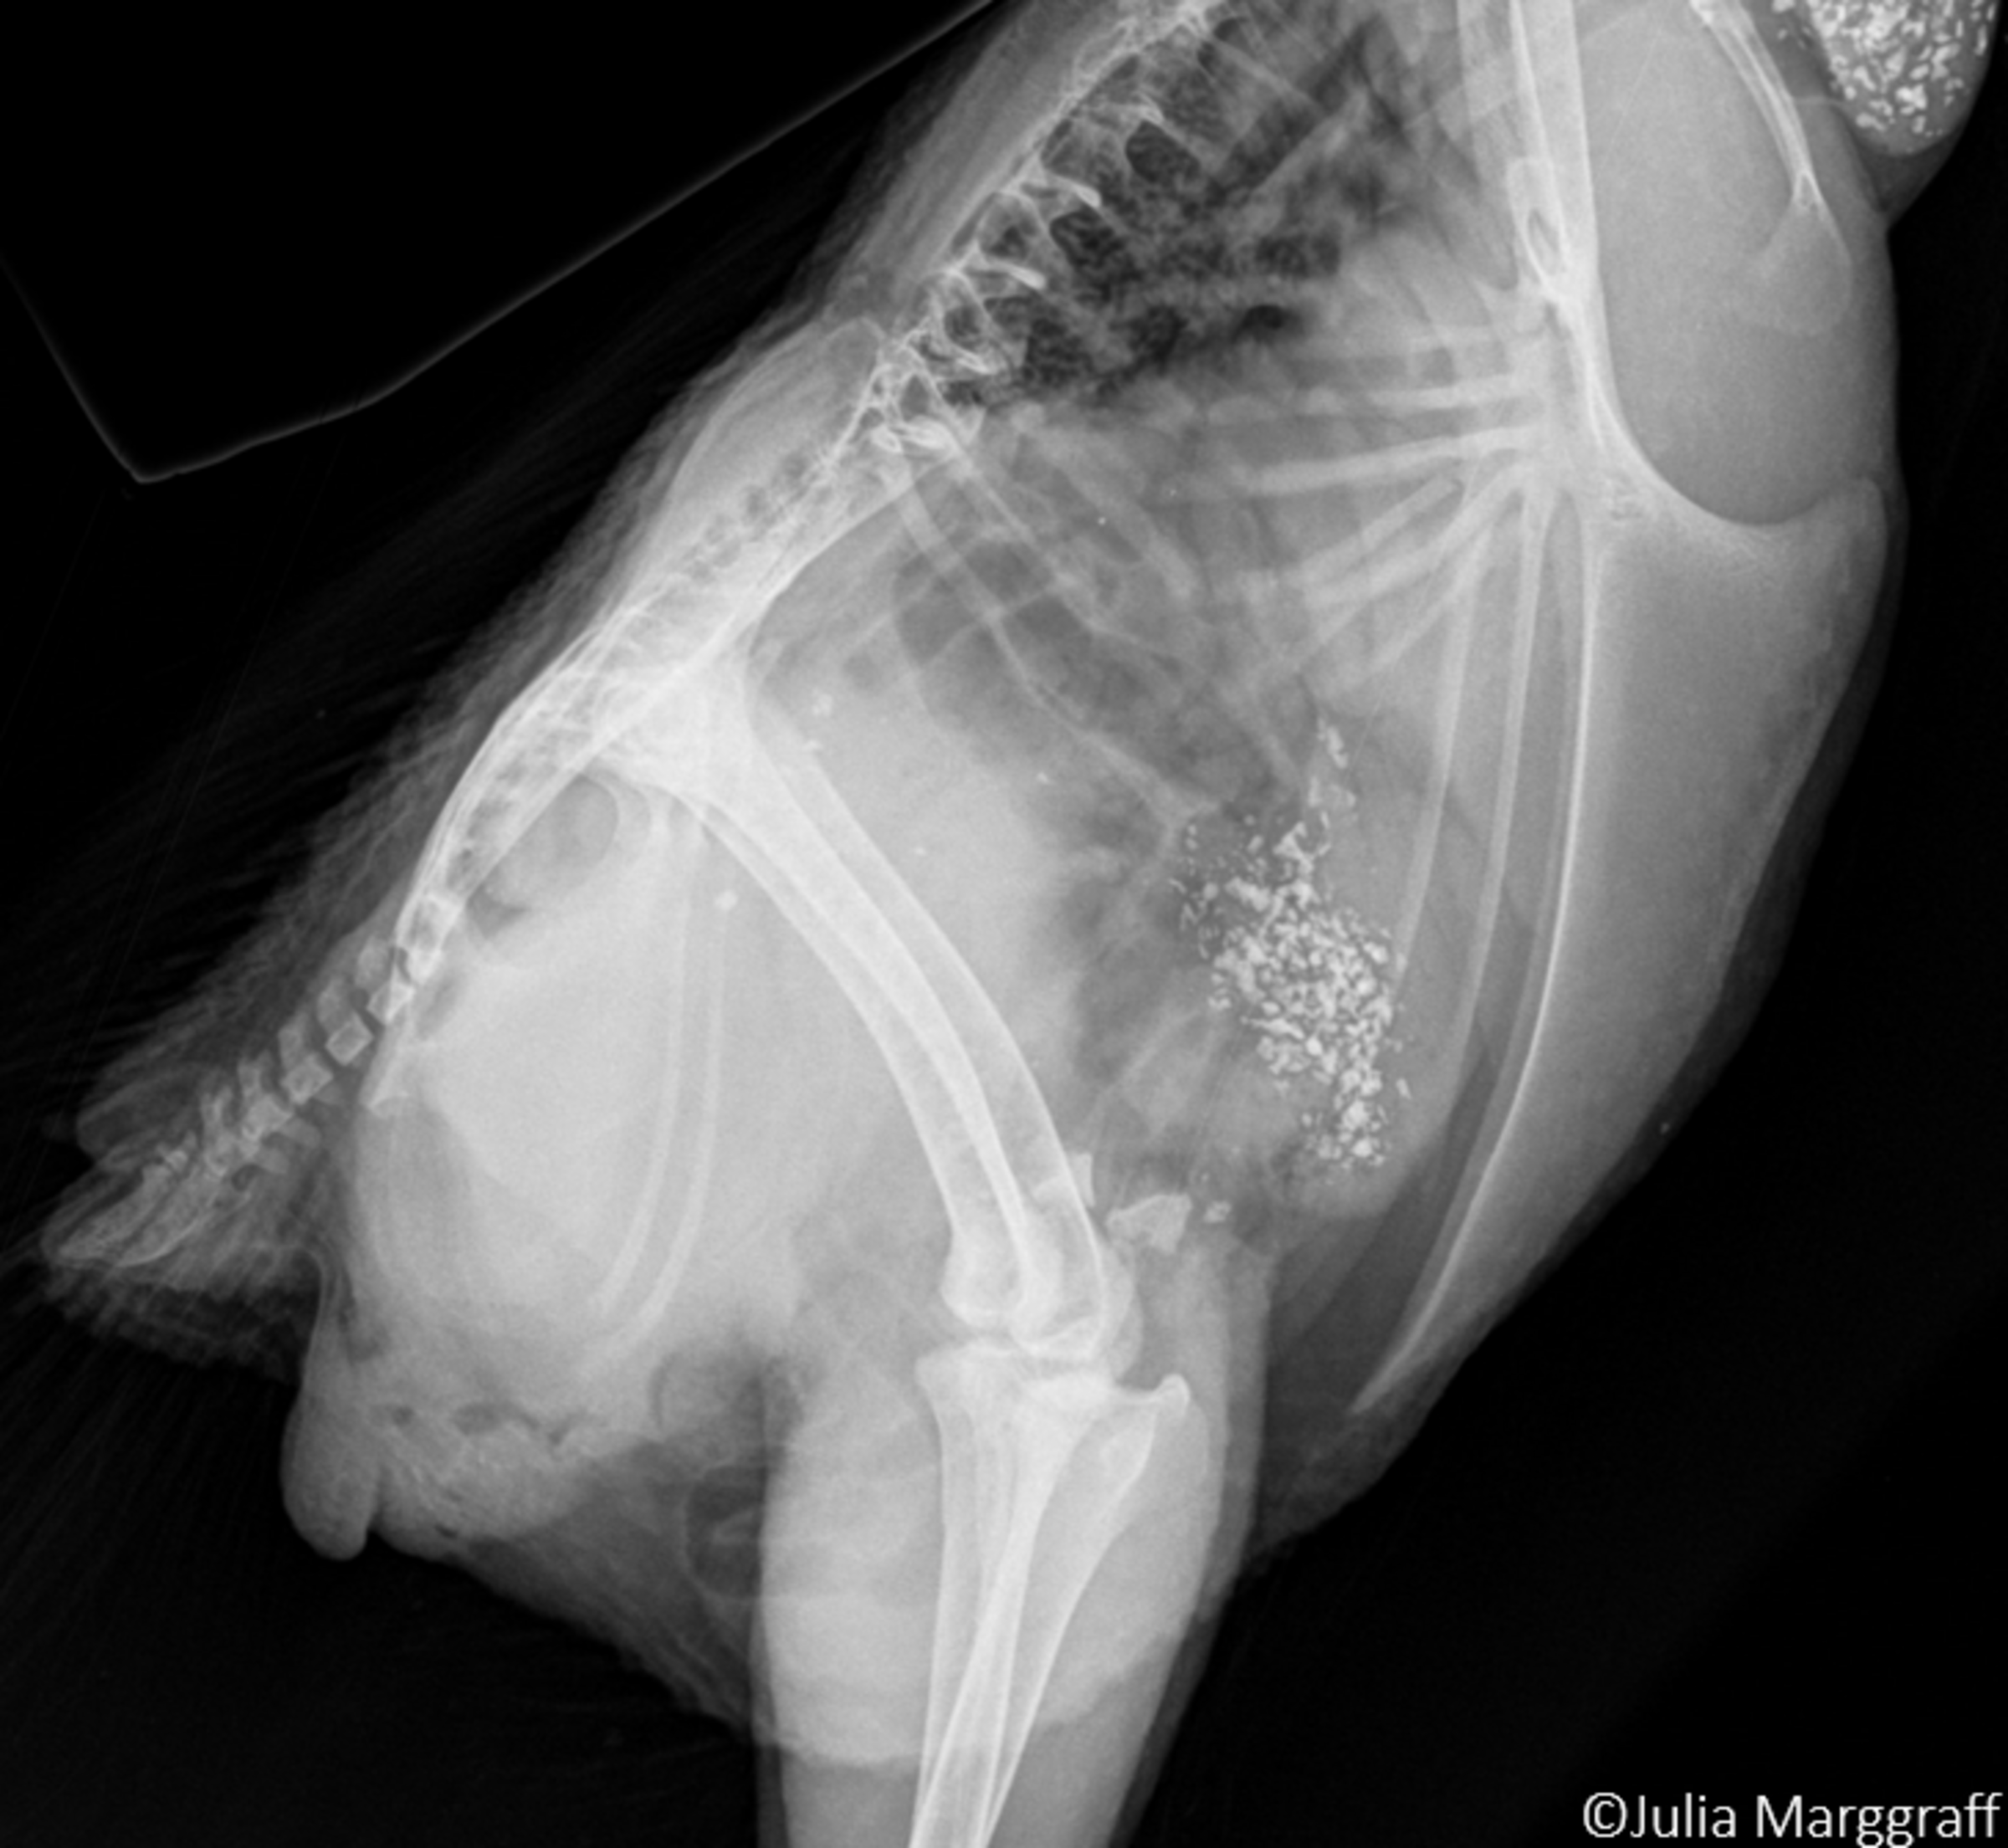

Bei Knochenbrüchen wird zwischen traumatisch bedingten und atraumatischen Frakturen unterschieden. Im Gegensatz zur traumatisch bedingten fehlt bei der atraumatischen Fraktur eine externe Krafteinwirkung als Ursache (z.B. Aufprallen auf eine harte Kante). Bei diesen Frakturen sind die Frakturenden am Knochen oft sehr dicht beisammen und die Knochenhaut bleibt intakt. Im Röntgenbild stellen sie sich als feine Haarrisse dar. Diese Frakturen treten meist bei älteren Hennen als Folge von Knochenermüdungen oder Osteoporose auf. Bei traumatisch bedingten Frakturen ist der Schweregrad abhängig von der Krafteinwirkung. Je schwerwiegender die Kollision im Haltungssystem oder je größer die Kraft, desto größer der Zerstörungsgrad am Knochen. Das Spektrum reicht dabei von kleinen abgebrochenen Knochenenden bis zu schweren Trümmer- oder Splitterfrakturen. Im Lauf der Haltungsperiode kann das Brustbein einer Legehenne mehrmals brechen. Beide beschriebenen Frakturformen können am selben Tier auftreten.

Da in den wenigsten Ställen Röntgengeräte zum Einsatz kommen, die für das Feststellen von Knochenbrüchen optimal wären, greift man auf die Methodik der Palpation zurück. Dabei tastet der Untersucher das Brustbein einzelner Hennen ab und erfühlt Abweichungen der „normalen“ Brustbeinform.